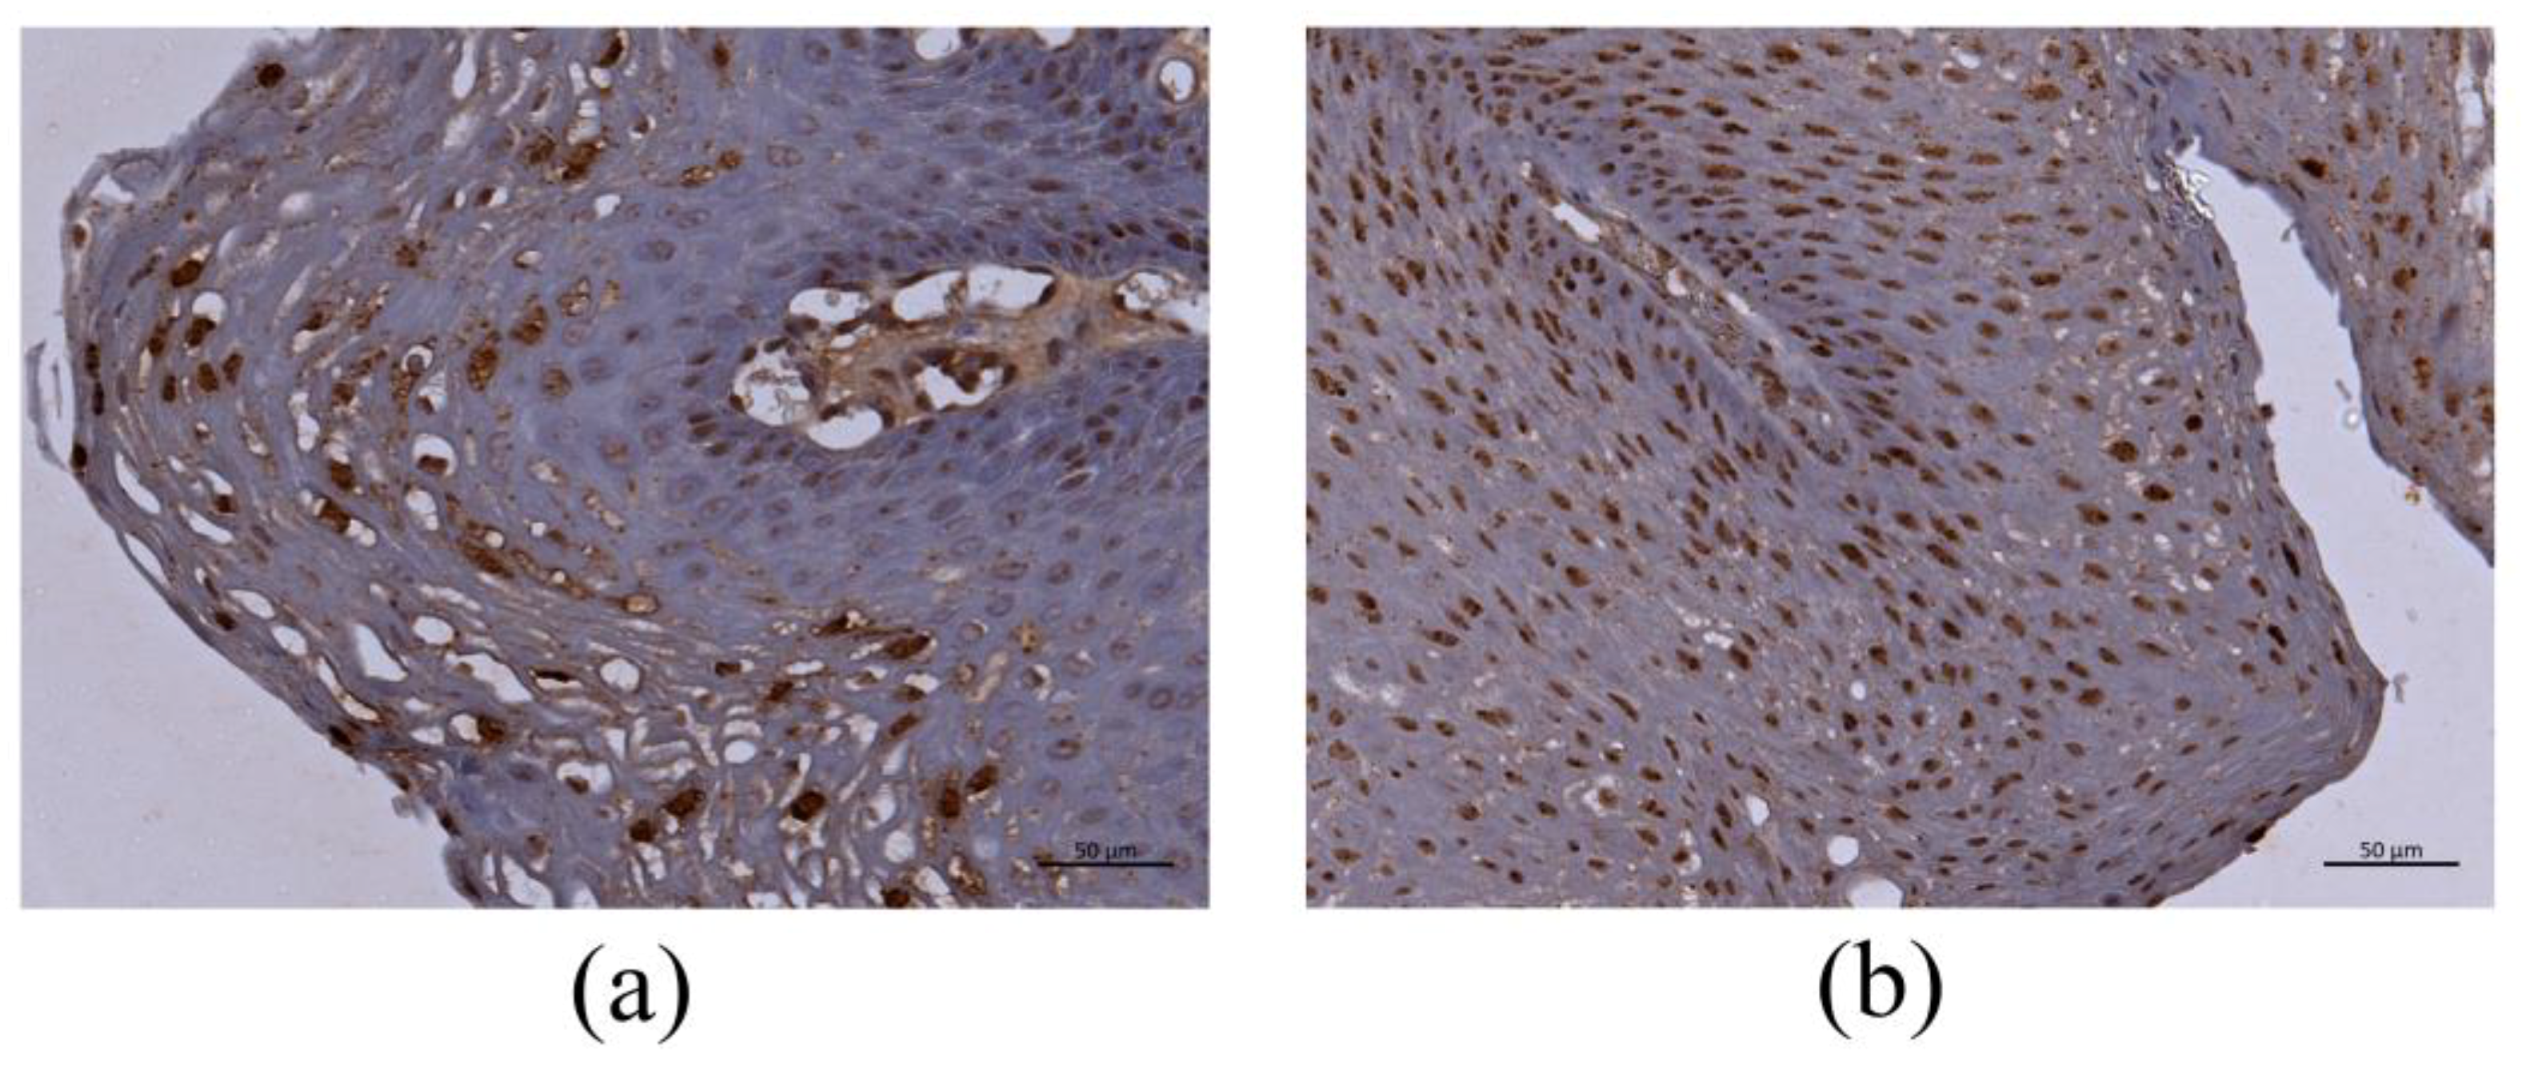

3.3. Immunohistochemistry for HPV-6 E1^E4